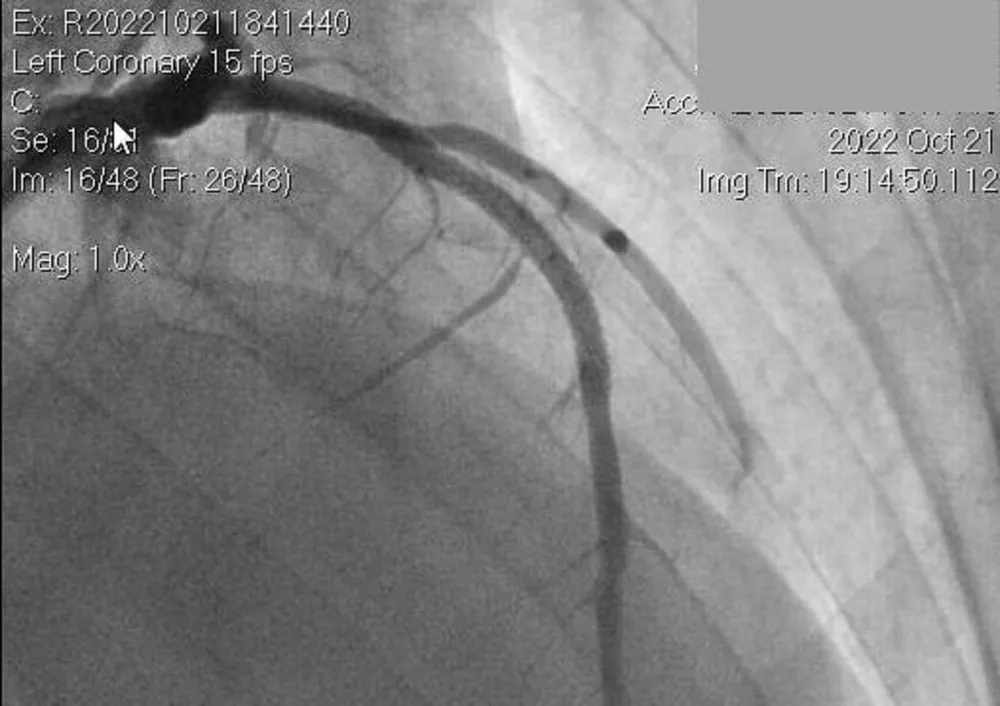

Hình ảnh chụp mạch máu của bệnh nhân THT. Ảnh: BVCC |

Điện tim trên monitor cho thấy bệnh nhân có tình trạng nhồi máu cơ tim thành trước rộng, êkíp cấp cứu hội chẩn liên viện với chuyên gia của BV Nguyễn Tri Phương qua điện thoại để được tư vấn về chuyên môn, đồng thời đề nghị chuyển bệnh nhân về BV Nguyễn Tri Phương.

Sau khi tiếp nhận, êkíp trực cấp cứu của BV Nguyễn Tri Phương hội chẩn với BS chuyên khoa tim mạch can thiệp, chẩn đoán đây là trường hợp nhồi máu cơ tim cấp thành trước rộng giờ đầu, biến chứng ngưng tim ngoại viện đã được hồi sức thành công. Chỉ định phải tái thông mạch vành cấp cứu.

Sau 30 phút can thiệp, bệnh nhân đã được thông tắc một nhánh động mạch vành lớn nhất, sau đó chuyển về khoa tim mạch can thiệp theo dõi và điều trị tiếp.